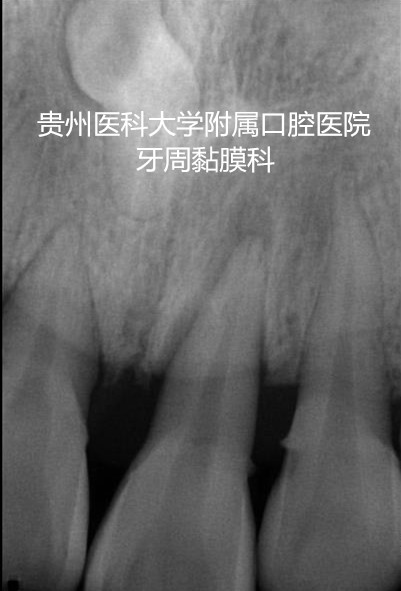

陈老师是一名重度牙周炎的患者,上下前牙多颗牙松动严重,经过牙周系统治疗后,牙周的炎症得到控制,但上下前牙的松动仍影响咬合,经过91直播

牙周黏膜科的高强度纤维带松牙固定后,将多个松动牙连成一个新的咀嚼单位,有利于牙周组织的愈合,陈老师非常满意。